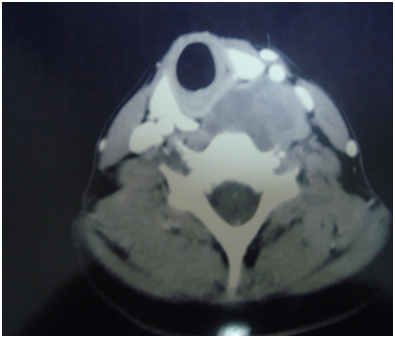

On radiological evaluation, computerized tomography scan of neck showed a large mass evolving the left prevertebral muscle from the mid neck to the thoracic inlet causing a displacement of the carotid and the jugular vein in anterior direction (Figure 1).

Figure 1 CT scan of neck, axial view, showing a large mass involving the left prevertebral muscle from the mid neck to the thoracic inlet displacing the carotid and the jugular vein anteriorly.